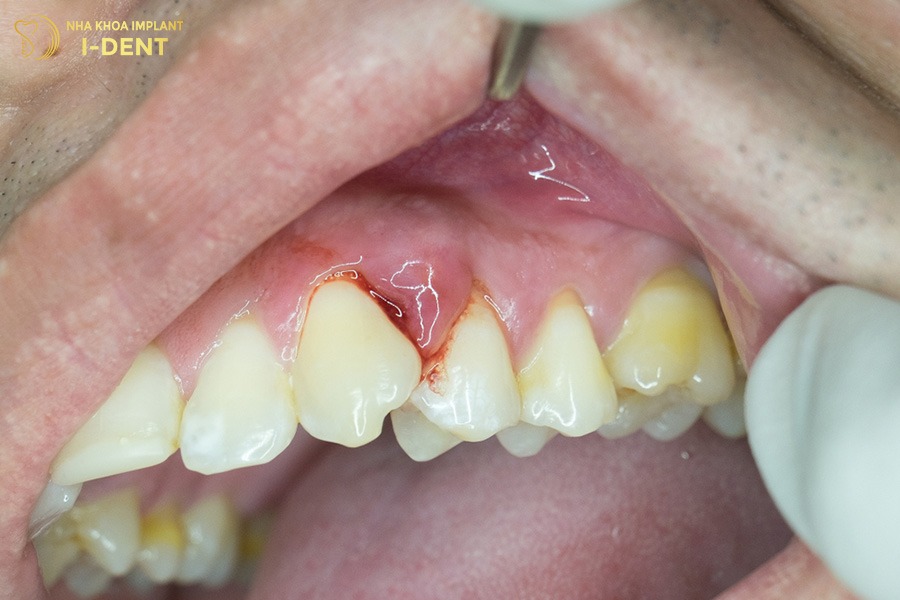

2.3. Nướu sưng đỏ và chảy máu chân răng

Một trong những dấu hiệu sớm của tiêu xương răng là nướu bị sưng, nướu có màu đỏ và dễ chảy máu chân răng khi chải răng hoặc ăn nhai. Nguyên nhân chủ yếu đến từ việc vệ sinh răng miệng chưa đúng cách, khiến mảng bám và cao răng tích tụ lâu ngày, tạo môi trường thuận lợi cho vi khuẩn phát triển và gây viêm. Ngoài ra, viêm nướu còn gây hôi miệng, ảnh hưởng đến giao tiếp và chất lượng cuộc sống.

Nướu sưng đỏ và chảy máu khi chải răng.

2.4. Nướu tụt và thân răng dài lộ ra

Khi xương ổ răng bị tiêu giảm, phần mô nướu phía trên cũng tụt dần xuống làm cho phần chân răng lộ ra trông dài hơn bình thường. Bên cạnh đó, vi khuẩn có thể xâm nhập sâu vào mô nướu, gây nhiễm trùng và làm xương ổ răng tiêu dần theo thời gian. Nếu không được điều trị thì nướu sẽ tiếp tục tụt sâu hơn, làm tăng nguy cơ viêm nha chu, lung lay răng hoặc mất răng vĩnh viễn. Đây được xem là hiện tượng răng bị tiêu xương ngay cả khi không bị mất răng.

Nướu tụt khiến thân răng trông dài hơn.